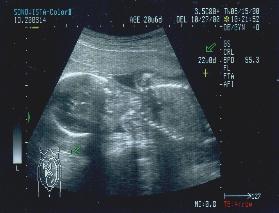

はじめての経膣超音波 (妊娠4周〜5週) : 当院ではほぼすべて超音波は妊婦さんにもお見せします。

あかちゃんのはいる袋(胎嚢)の確認。

胎嚢の大きさは12mm(子宮の中にちゃんと着床しているかの確認)。

あかちゃん(胎児)の成長(妊娠7週)

あかちゃんは棒のように見え始め約10mmくらいです。

小さくても心臓はしっかりと動いているのが見えます。